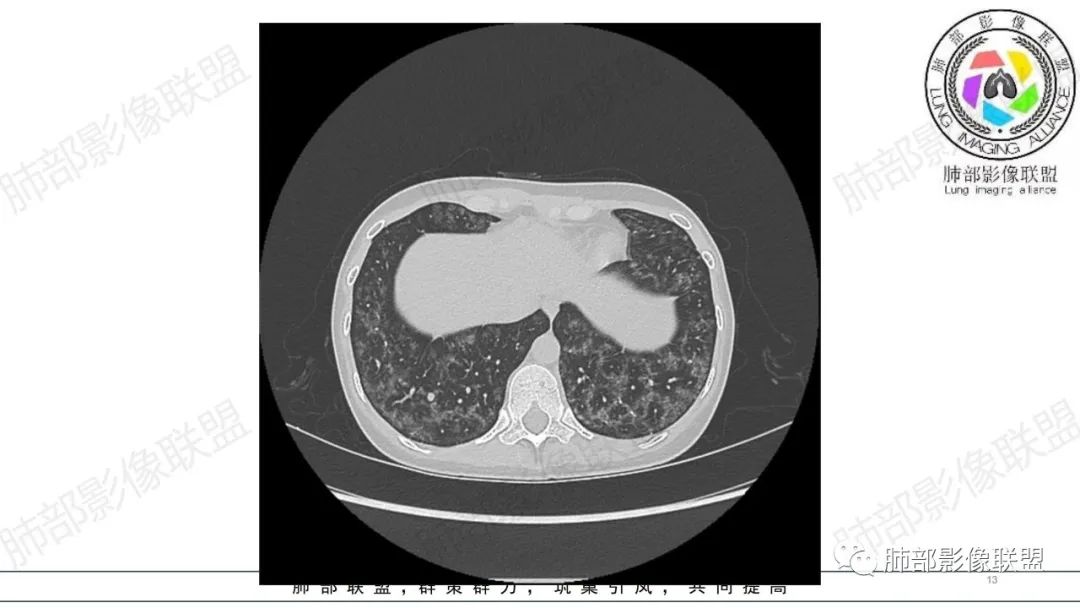

影像资料

34岁女性患者,“哮喘”病史30年,近期有可疑刺激性气体吸入史;因乏力半年,咳嗽、憋气、发热4天就诊;6.1CT提示双肺广泛毛玻璃影及粟粒样结节,胸膜下闲置及血管周闲置,可见树丫征,部分小叶间隔增厚。考虑:1.过敏性肺泡炎,有可疑刺激气体接触史,胸膜下闲置,广泛毛玻璃影,地图样分布,粟粒结节边界模糊,支持过敏性肺泡炎,但糖皮激素治疗效果不佳,且动态复查血常规血红蛋白进行性降低,过敏性肺泡炎 不符合;2.肺含铁血黄素沉积症:患者30“哮喘”病史,可能为肺含铁症状,肺部CT提示双肺弥漫毛玻璃影及粟粒结节影,中下肺明显,肺底部分小叶间隔增厚,近期咳嗽、憋气、发热,血常规血红蛋白进行性下降,考虑肺含铁急性期症状,但临床无咯血症状,肺含铁不典型。综合考虑:肺含铁血黄素沉积症>过敏性肺泡炎。

年轻女性 ,急性喘息发热,肺部影像弥漫磨玻璃密度,部分细小腺泡结节,胸膜下黑线显示,短期复查,病变密度增高,下肺明显,血管周围肺组织累及较少、且逐渐成小叶间隔分布。考虑弥漫肺泡内病变,并经淋巴道转移,下肺比上肺明显,多为免疫细胞功能下肺较强。1.过敏性肺泡炎,有相关病史,三层密度特点、头尾测分布,符合。2 肺泡微石症,多有钙化,且缓慢起病,病程不太符合,放待排。3 吸入相关肺损伤,有病史,疾病演变过程也符合渗出-肉芽肿改变,建议详细询问病史。4 感染性病变,结核?病变气道分布为主,如此弥漫且没有树丫不符合。5.巨细胞病毒,可以磨玻璃 结节 改变,没有免疫缺陷病史。最后考虑吸入所致 1过敏性肺泡炎、吸入性肺损伤 鉴别肺泡微石症。

肺内气腔磨玻璃结节,肝脾肿大,治疗后间质改变,弥漫大B可能